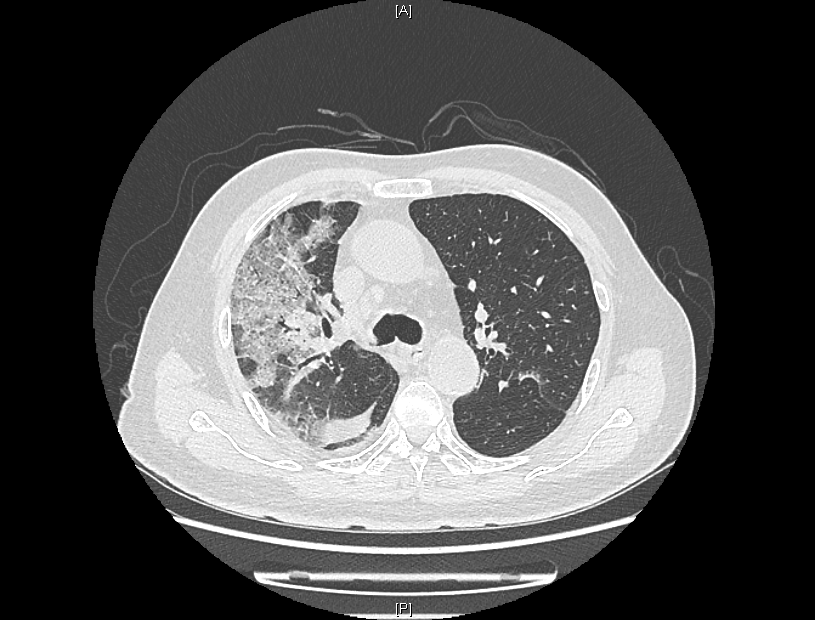

患者肺部CT检查图像

来院时,患者感染新冠病毒5天,持续发烧不退,出现了憋气、意识不清。患者入院后,经过医院持续监察发现,患者肺部CT逐步呈“白肺”状态,血气氧分压一度降至50mmHg,“正常血气氧分压为80-100mmHg,低于60mmHg,在临床上就可诊断为I型呼吸衰竭。”感染性疾病科主任林明贵说。